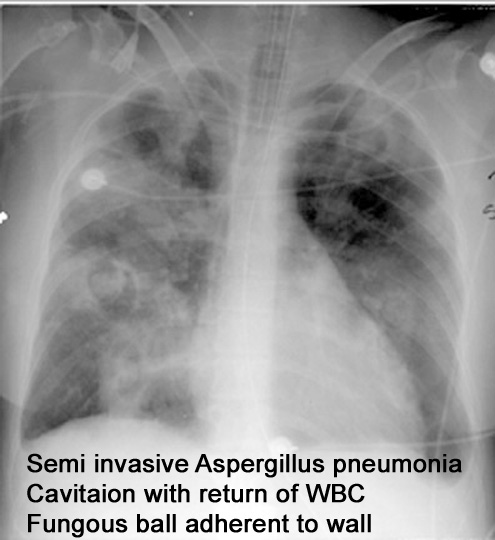

What is semi invasive aspegillosis?